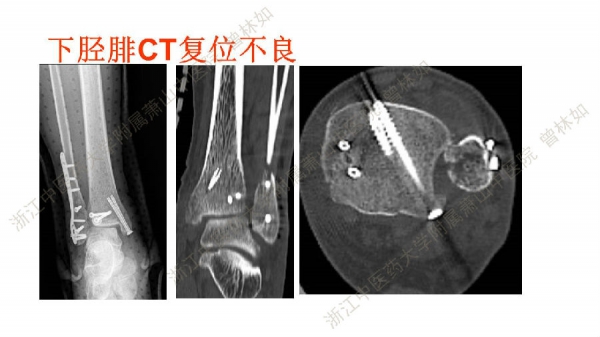

2017-06-13 文章来源:浙江中医药大学附属萧山中医院 作者:曾林如 我要说